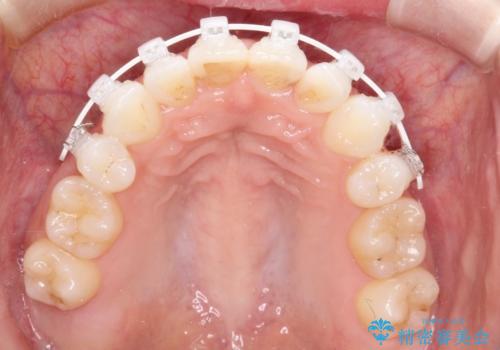

- 矯正装置

- 審美装置

- 矯正治療後の上の前歯の後戻りを気にされて来院されました。

上の前歯のみにブラケットをつけて矯正治療を行いました。